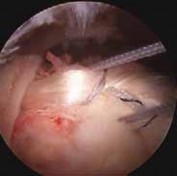

2. Long head of biceps tendinopathy encompasses a spectrum of pathology, including intratendinous signal change, synovitis of the sheath, partial tearing, and frank tendon rupture (

FIG 2

).

A

B

FIG 2 • Arthroscopic images of tendinopathy and tearing of the long head of the biceps tendon. NATURAL HISTORY 8. Little is known about the natural history of biceps tendinopathy, so prediction of a patient’s clinical course is difficult.